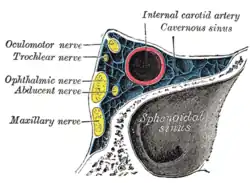

In der Cisterna ambiens des Subarachnoidalraums windet er sich seitlich um den Hirnschenkel (Pedunculus cerebri) an die Basis des Hirnstamms und verläuft hier zwischen der Arteria cerebri posterior und der Arteria superior cerebelli. Etwa in Höhe der Türkensattellehne (Dorsum sellae [turcicae]) durchsetzt er am Rand des Tentoriumschlitzes (Incisura tentorii) die Dura und verläuft in der Seitenwand des venösen Sinus cavernosus. Hier liegt der Nervus trochlearis (N. IV) zwischen dem Nervus oculomotorius (N. III) und dem Nervus ophthalmicus (N. V1).